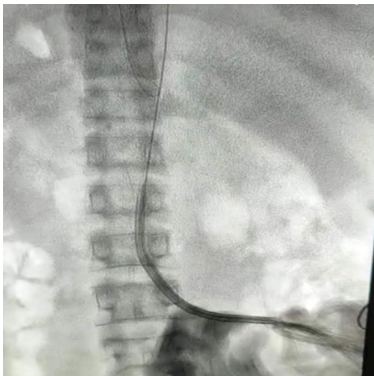

经腰导管置入:俯卧位下超声引导穿刺IVC,建立皮下隧道后置入14.5F带袖双腔导管。如图1所示,导管尖端需达右心房水平。